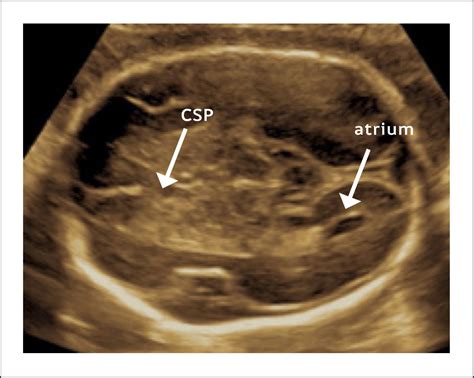

The Cavum Septum Pellucidum is a thin, fluid-filled space that lies between the two layers of the septum pellucidum, a membrane that separates the lateral ventricles of the brain. The septum pellucidum itself is a thin, triangular membrane that extends from the corpus callosum to the fornix. The Cavum Septum Pellucidum is typically present in the developing brain and usually closes during fetal development. However, in some individuals, it may persist into adulthood, a condition known as cavum septum pellucidum.

Diagnostic imaging techniques, such as magnetic resonance imaging (MRI), are essential for visualizing the Cavum Septum Pellucidum and assessing its size and shape. MRI provides high-resolution images of the brain, allowing clinicians to detect abnormalities in the Cavum Septum Pellucidum and other structures.

MRI is the preferred imaging technique for evaluating the Cavum Septum Pellucidum due to its high resolution and ability to differentiate between soft tissues. CT scans and PET scans may also be used in specific clinical contexts, but they are less commonly employed for assessing the Cavum Septum Pellucidum.

- cavum septum pellucidum fetal ultrasound